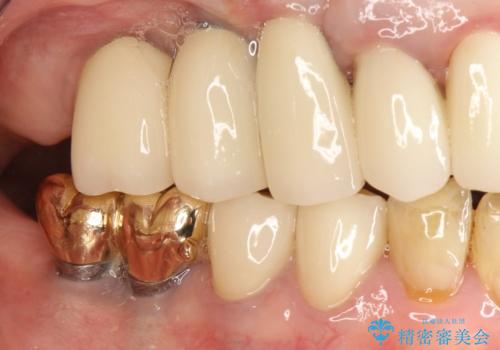

かぶせ物の種類:PFZ

薄い骨にもインプラントを スプリットクレスト+ショートインプラントの応用